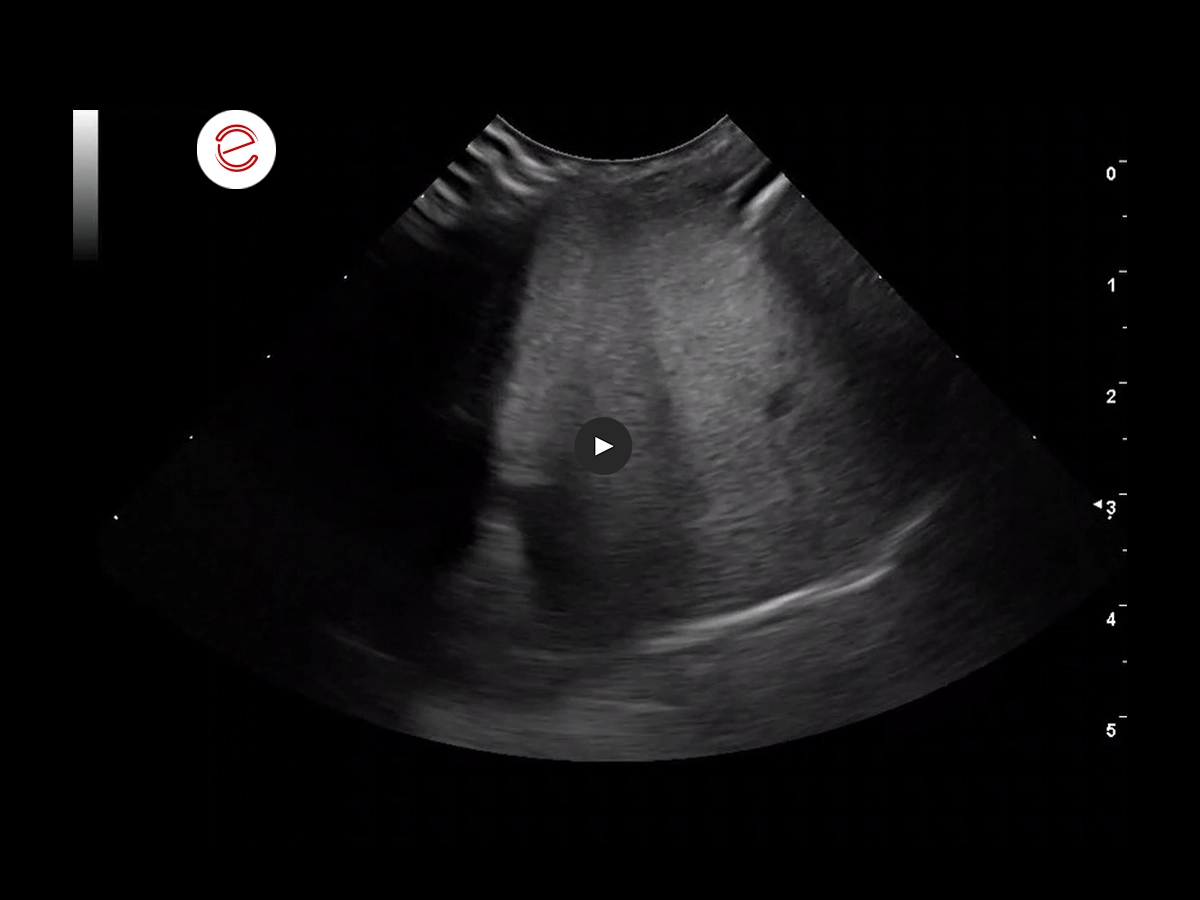

2 months before the respiratory issues: the larger right liver lobe is visible in the sagittal ventromedial view. The liver appears dense and heterogeneous, and the small hepatic vessels appear compressed.

The microV function outlines the compressed vessels.